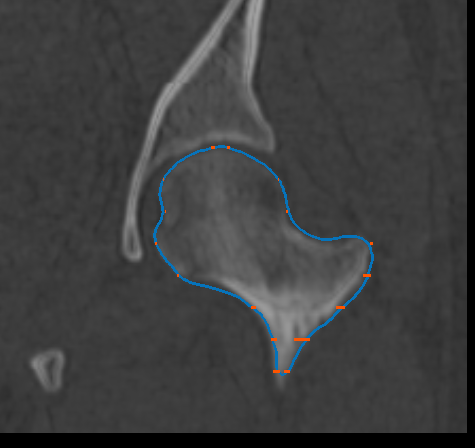

You can generate a mesh surface that fully describes a feature of interest or anatomy after you have created a group of paths that outlines the feature of interest or anatomy (see Creating Groups of Paths). Options for optimizing mesh surface generation can be selected in the Mesh surface tab (see Mesh Surface Settings).

Mesh surfaces are calculated from the point clods on each path and the selected normals.